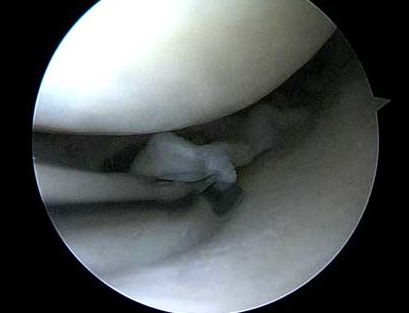

Menisksutur-Reparation

- Menisken sys fast och bevaras i sin helhet.

- Operationen går oftast att göra med titthålsteknik men ibland behöver det kompletteras med ett litet hudsnitt

- Menisksuturen måste skyddas med ett knäskydd under 6 veckor efter operationen.

- Läkningsfrekvens om det görs i samband med ligamentrekonstruktion ca 90 %.

- Läkningsfrekvens om det görs som isolerat ingrepp mellan 50-60 %.